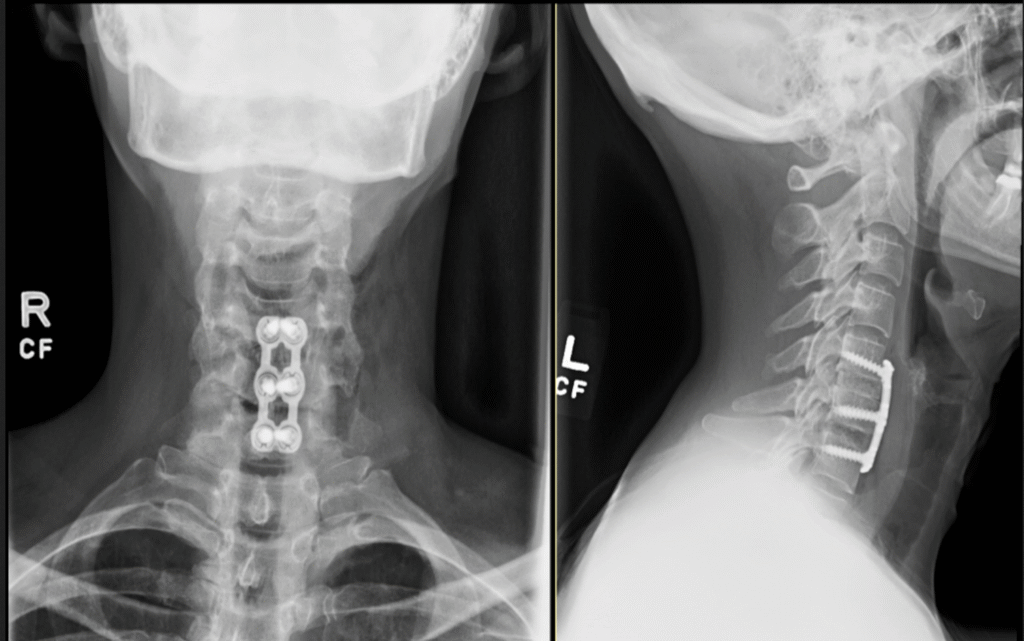

TDR 1024x626

Screen Shot 2017 08 31 At 11.02.09 PM 1024x620